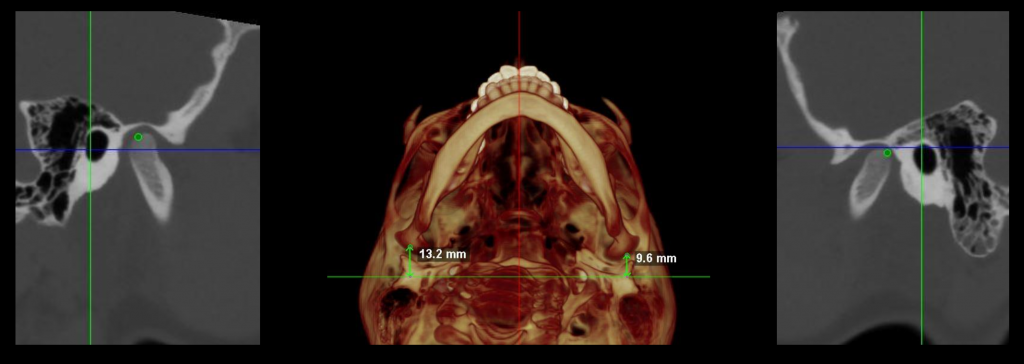

Estudios Personalizados

Cada paciente y cada tratamiento es único. El profundo conocimiento de la anatomía y de nuestros pacientes junto con la tecnología más avanzada nos permite realizar diagnósticos certeros. Localizando el origen del problema muchas veces incluso antes de que se produzca evitando así su aparición.